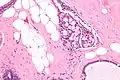

| Micrograph of collagenous spherulosis with the characteristic histomorphology - intratubular eosinophilic material with a spoke-like arrangement. H&E stain. | |

Collagenous spherulosis is characterized by a tubular/cribriform architecture with intratubular eosinophilic material that classically is arranged like the spokes of a wheel ("radial spikes"). There is usually no mitotic activity, and two cells populations (epithelial & myoepithelial) are present, like in benign breast glands.